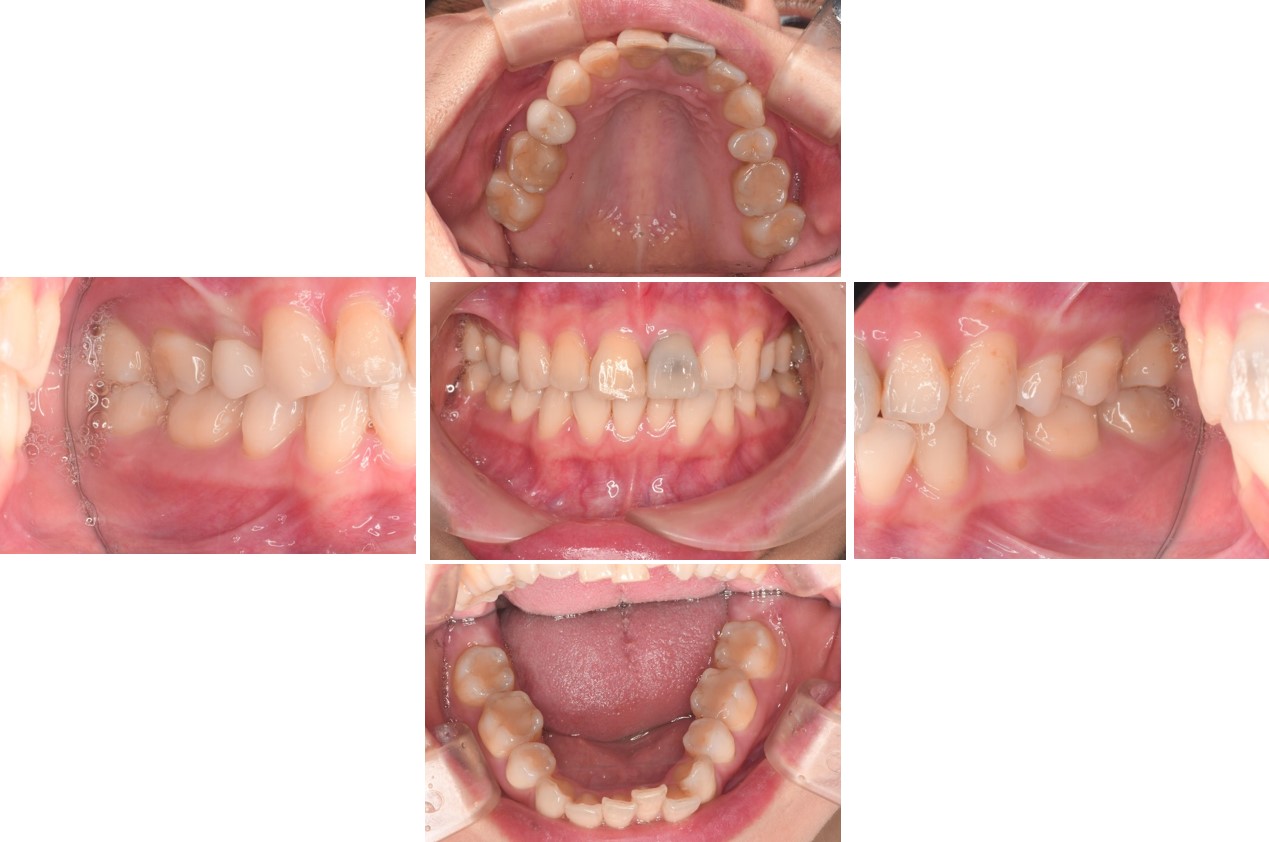

初診口內照,前牙美觀不良

下顎前牙過度萌出,咬合不正